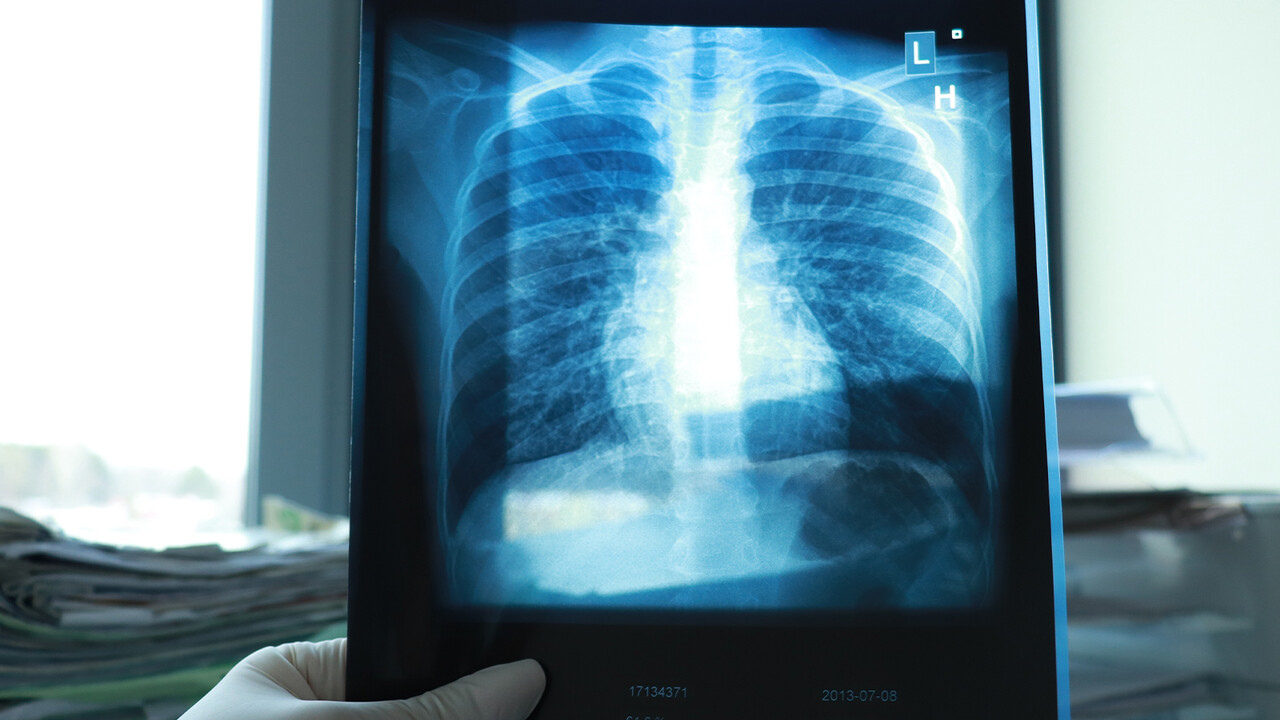

Uzm. Dr. Demet Çetin, özellikle sonbahar ve kış aylarında bağışıklığı zayıf olan yaşlılar, çocuklar ve kronik hastaların daha dikkatli olması gerektiğini belirtti. Grip, nezle veya COVID-19 gibi viral enfeksiyonların sonrasında bağışıklık sisteminin zayıfladığını vurgulayarak, bu durumun bakterilerin akciğerlere daha kolay yerleşmesine ve zatürreye neden olmasına yol açabileceğini ifade etti. Zatürreyi, akciğer dokusunun iltihaplanması sonucu ortaya çıkan, ciddi seyirli bir enfeksiyon hastalığı olarak tanımladı.

Dr. Çetin, bu belirtilerden birisinin bile mevcut olması durumunda vakit kaybetmeden bir göğüs hastalıkları uzmanına başvurulması gerektiğini vurguladı. Zatürrenin basit bir soğuk algınlığı olmadığını ve gecikmiş vakalarda hastaneye yatış, hatta yoğun bakım desteği gerektirebileceğini ekledi.